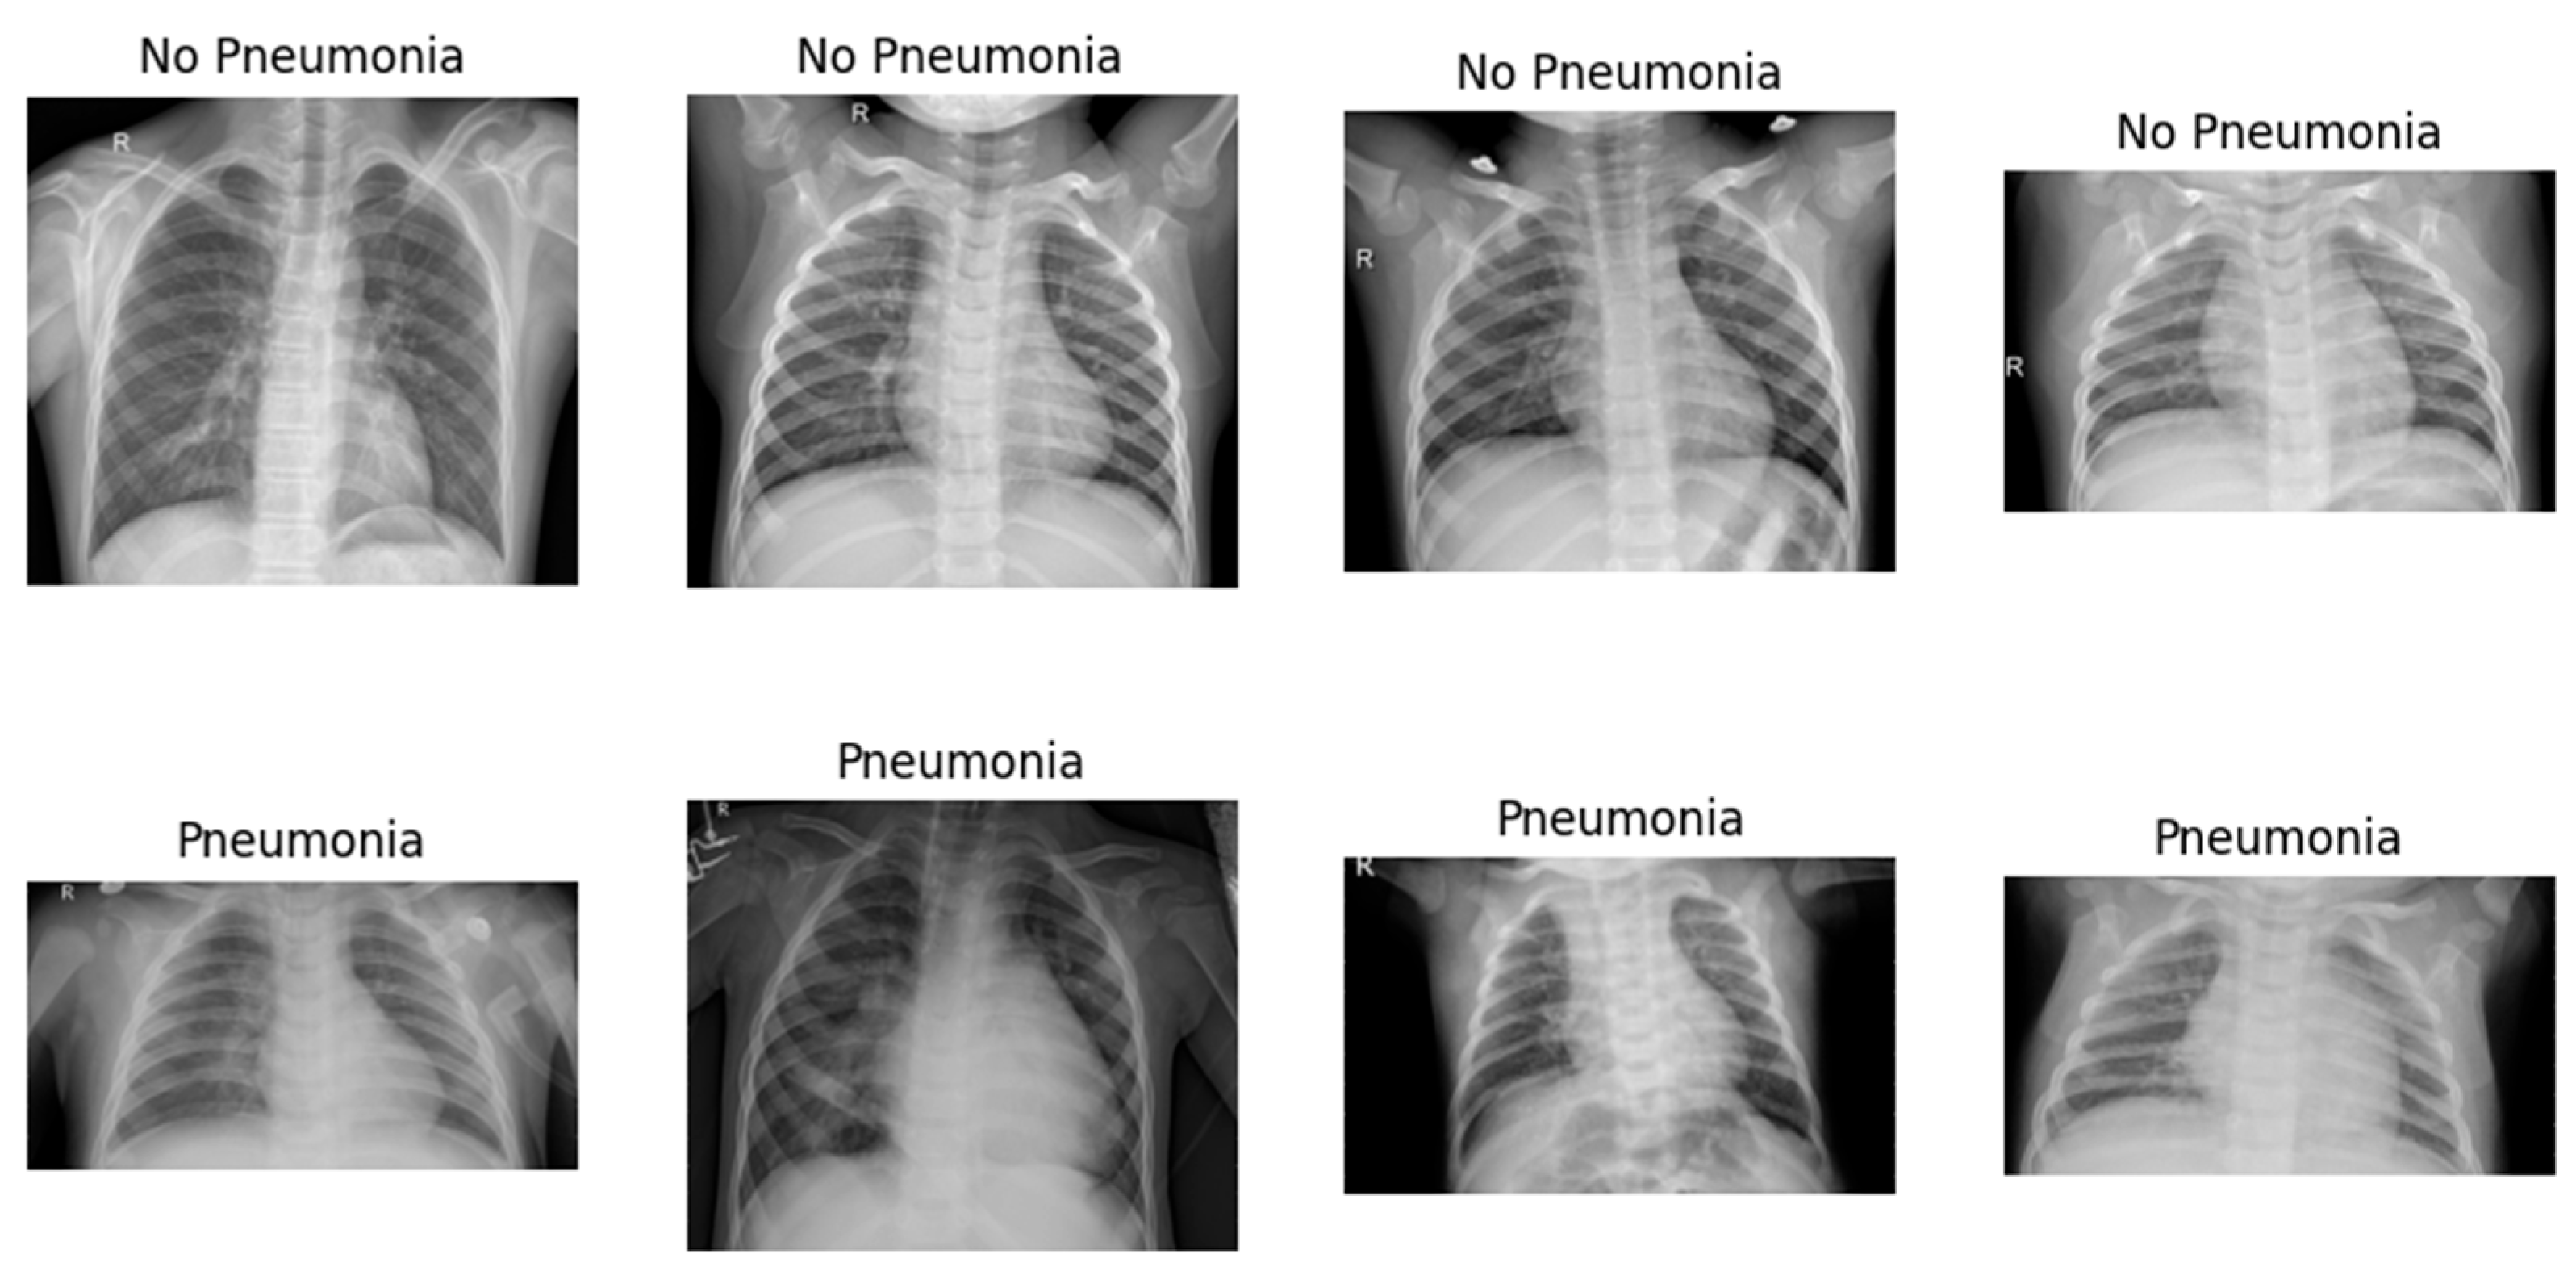

4.1. Dataset Description